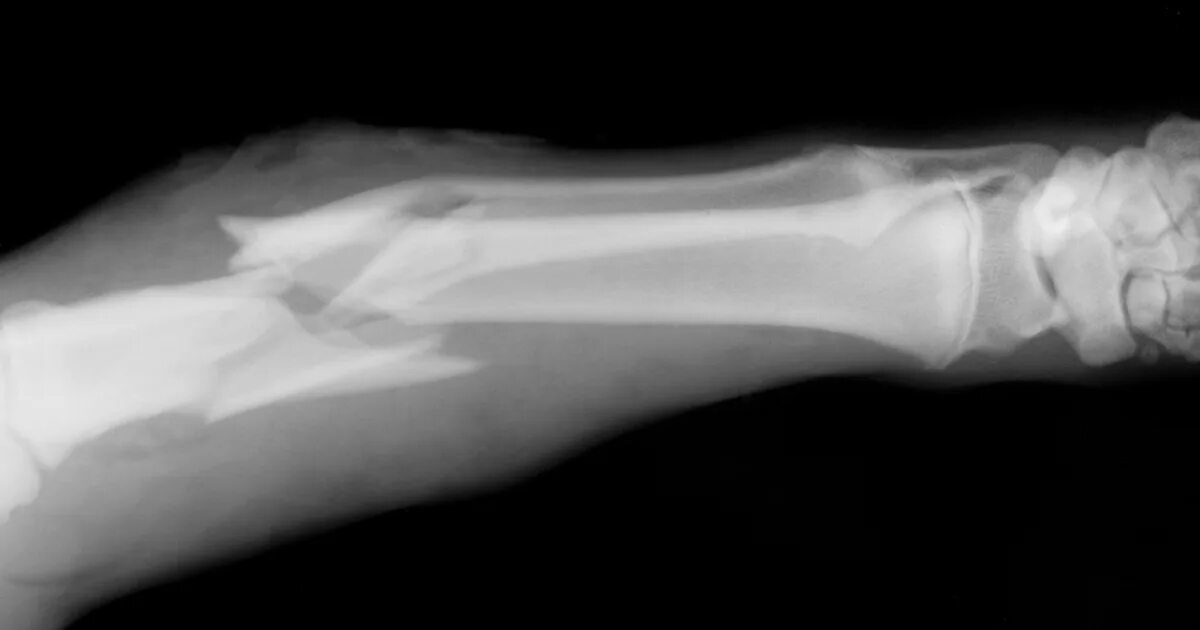

A fracture is a broken bone